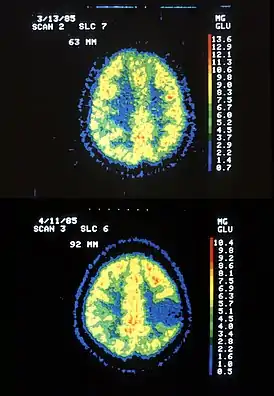

![]() Два ПЭТ изображения: верхнее показывает нормальный мозг, а нижнее — с астроцитомой. | |